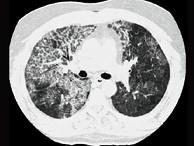

问题 24岁女性,咳嗽、进行性胸闷、气促2月,支气管镜如图,镜下可见大量米汁样分泌物。影像学检查如图。可能的诊断是 ( )

选项 A.肺泡蛋白沉积症 B.支气管扩张 C.肺炎 D.肺结核 E.先天性肺囊肿

答案 A